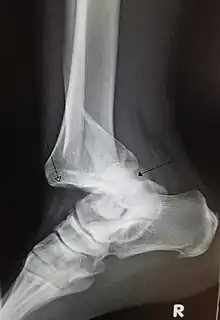

![]() | |

| A traumatic dislocation of the tibiotarsal joint of the ankle with distal fibular fracture. Open arrow marks the tibia and the closed arrow marks the talus. | |